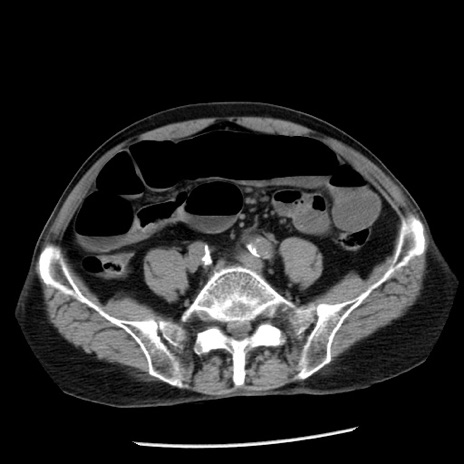

症例26(横断像)

【症例】80歳代男性

【主訴】嘔吐

【現病歴】昨晩2回嘔吐あり、今朝になっても嘔吐あり。来院。

【既往歴】胃潰瘍

【身体所見】意識清明、BT 37.6℃、BP 166/95mmHg、HR 100bpm、SpO2 97%、腹部:平坦・軟、腸蠕動音聴取良好、圧痛なし。

【データ】WBC 21900、CRP 1.46